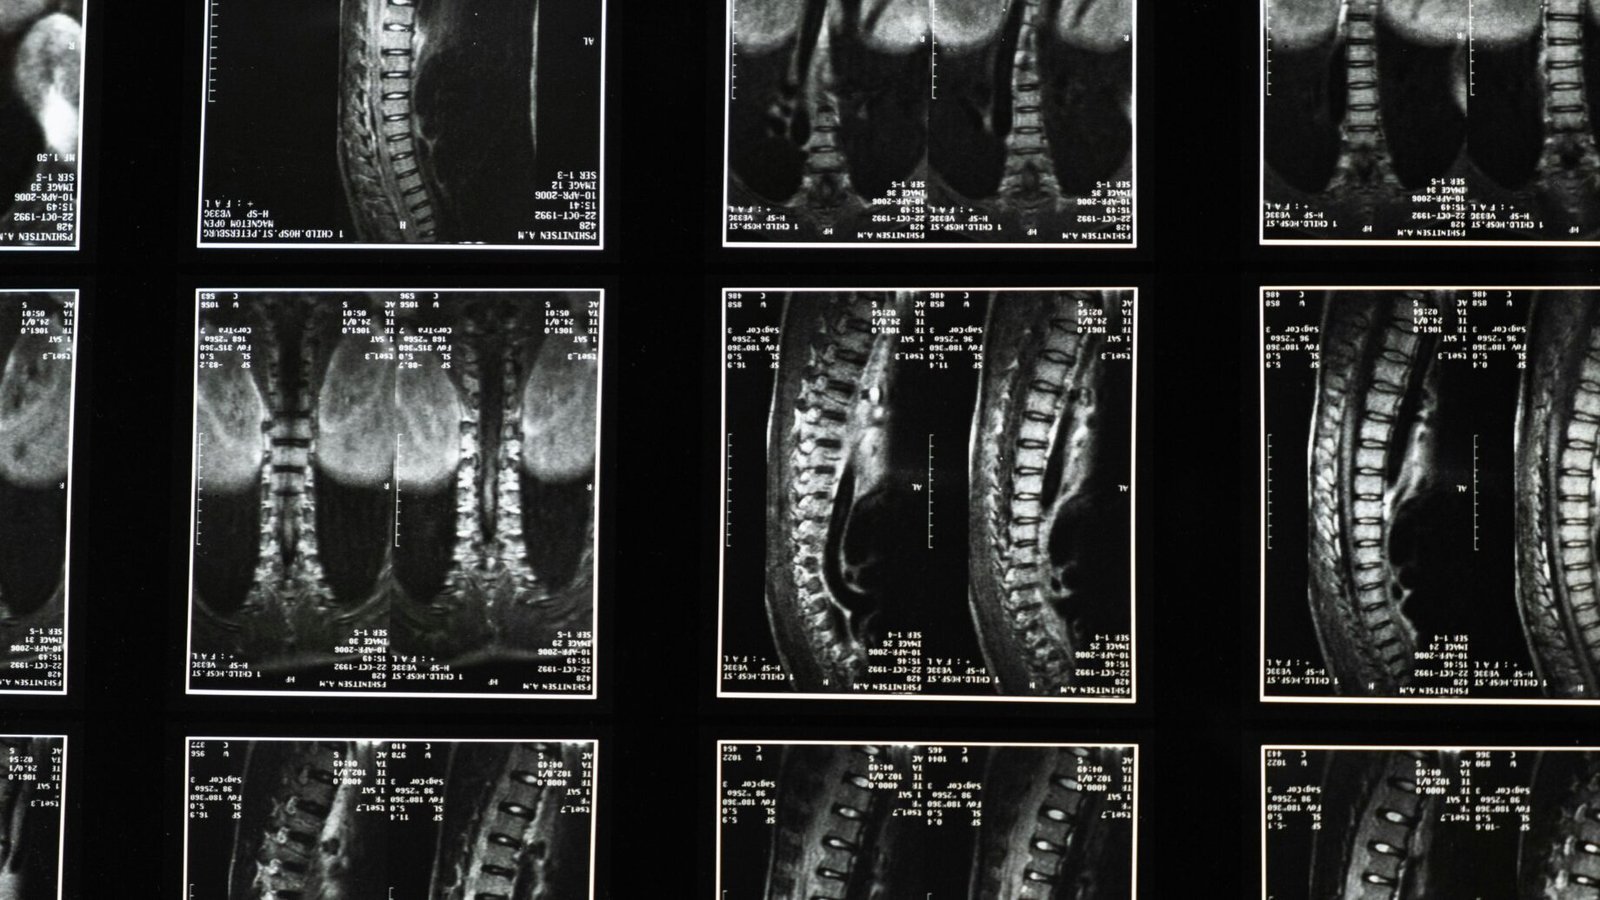

A quiropraxia é uma profissão da saúde que se dedica ao diagnóstico, tratamento e prevenção de distúrbios do sistema neuromusculoesquelético, com foco principal na coluna vertebral. A filosofia central da quiropraxia é que a boa saúde depende de um sistema nervoso funcionando adequadamente, e que desalinhamentos vertebrais, conhecidos como subluxações, podem interferir nessa função, causando dor e outros problemas de saúde.

Um quiropraxista utiliza uma variedade de técnicas manuais, sendo a mais conhecida o ajuste vertebral. Este ajuste é um movimento preciso e controlado aplicado às articulações da coluna, com o objetivo de restaurar o movimento adequado, reduzir a dor e melhorar a função nervosa. Ao corrigir esses desalinhamentos, a quiropraxia busca otimizar a capacidade inata do corpo de se curar e funcionar em seu potencial máximo.